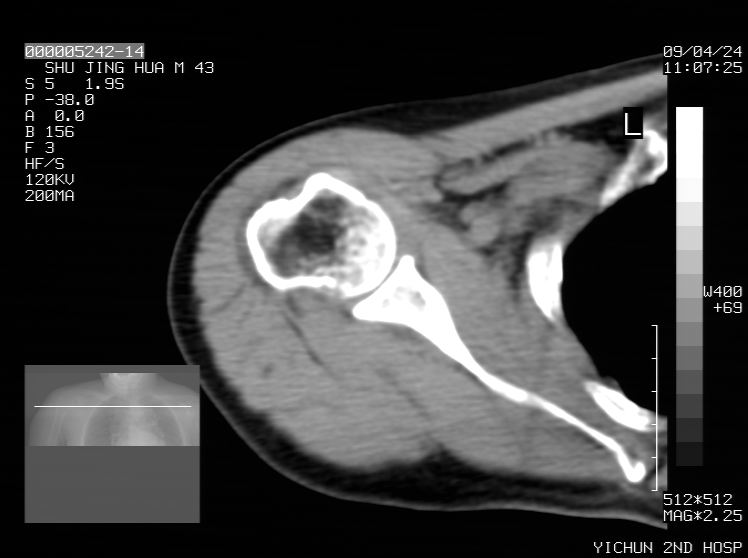

标题: CT19569:请会诊,女50岁,右肩疼痛数月 [打印本页]

标题: CT19569:请会诊,女50岁,右肩疼痛数月

钙化性肌腱炎

是指钙盐沉积在变性肌腱中的一种无菌性炎症,常见于肩关节的肩袖肌腱,引起肩部疼痛和活动受限。分为急性和慢性两种类型,急性型有肩关节突然出现急性疼痛的发作史,夜间可痛醒。

以下是引用余辉在2009-4-24 15:24:00的发言:[br]考虑钙化性肩周炎,肱二头肌长腱或相应附属组织钙化

支持